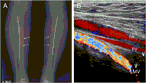

A rare presentation of Klippel–Trenaunay syndrome with bilateral lower limbs

Akira Baba and others

Journal of Surgical Case Reports, Volume 2017, Issue 2, February 2017, rjx024, https://doi.org/10.1093/jscr/rjx024